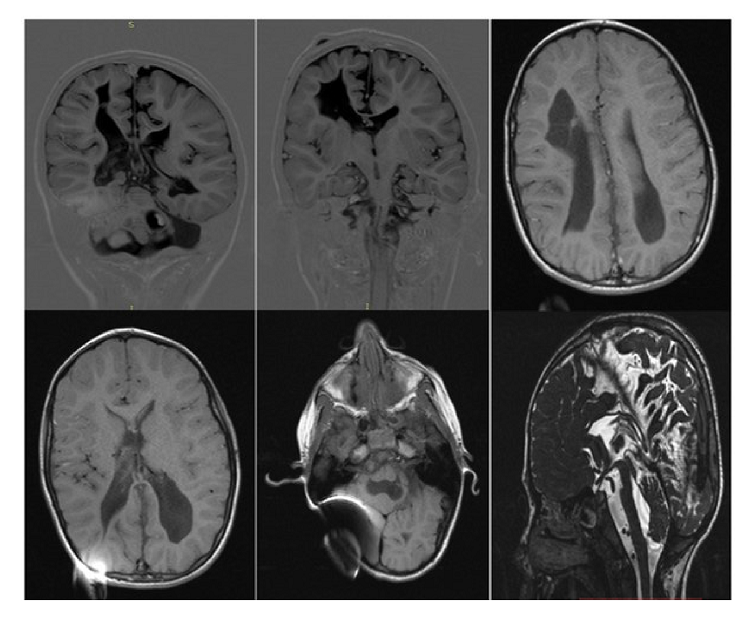

En cuanto al neurodesarrollo, tuvo sostén cefálico antes de los tres meses, sedestación y dominancia manual temprana a partir de los seis meses, control de esfínteres desde los tres años y marcha a los cuatro años. El examen neurológico a los siete años, anterior a la primera disfunción de la derivación ventrículo-peritoneal, se resumió así en la historia clínica: 'Alerta, lenguaje coherente, dislalia y disartria, espasticidad Ashworth 1 en hemicuerpo derecho y Ashworth 2 en hemicuerpo izquierdo, perímetro cefálico de 48 cm, buen contacto y seguimiento visual, limitación para la extensión del pie izquierdo y leve hiperreflexia en miembro inferior ipsilateral". La figura 1 corresponde a la imagen de resonancia magnética cerebral a esa edad.

A partir de los diez años, la paciente experimentó tres episodios sugestivos de falla del sistema de derivación ventrículo-peritoneal. En el cuadro 1 se resume cada uno de ellos, señalando la edad de la paciente, la presentación clínica, los estudios radiológicos, la conducta, y las deficiencias neurológicas y visuales presentes (figura 2).